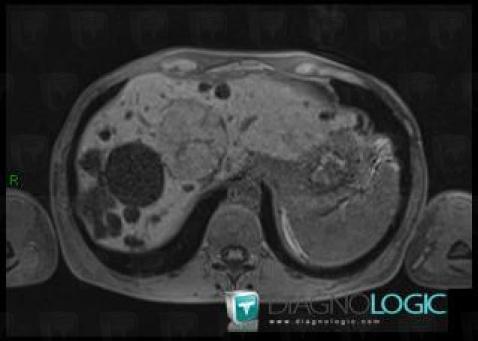

Hyperplasie nodulaire focale, Foie, IRM

Voici les informations spécifiques à l'image clé ci dessus:

- Diagnostic Hyperplasie nodulaire focale, Localisation(s) Foie, comportant les gammes Lésion hépatique en hypersignal T1

- Diagnostic Hyperplasie nodulaire focale, Localisation(s) Foie, comportant les gammes Lésion avec prise de contraste artérielle